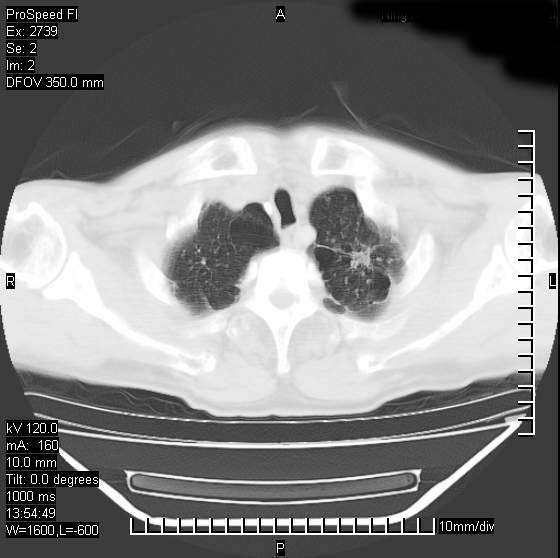

以下是引用andymaomao在2007-12-7 15:54:00的发言:[br]1.双上肺陈旧肺tb灶;[br]2.双中上肺矽肺;[br]3.双肺气肿;[br]4.图中箭头所指乃下腔静脉。

以下是引用山之魂海之韵在2007-12-7 18:59:00的发言:[br]支持矽肺,左肺上叶陈旧性结核,肺气肿。箭头所指乃下腔静脉。下腔静脉显影比主动脉显影迟,增强动脉后迟可以是不均匀的。

以下是引用chengjiaqiu1在2007-12-7 17:49:00的发言:[br]矽肺,左肺上叶陈旧性结核,肺气肿。中箭头所指乃下腔静脉。